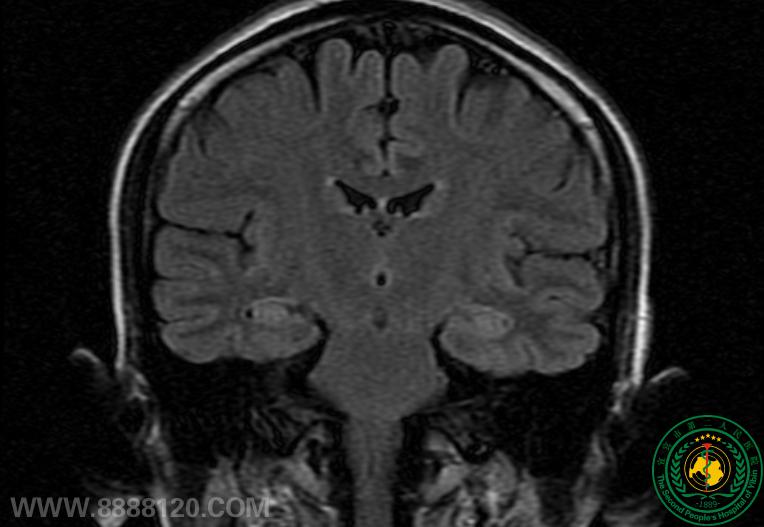

神外一科与神经内科合作共同治疗难治性颞叶癫痫一例

神外一科与神经内科合作共同治疗难治性颞叶癫痫一例6351